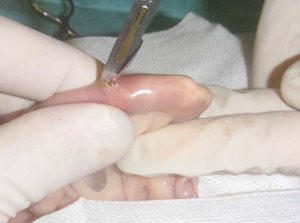

Photo 2

Un champ en plastique étanche est incisé et placé autour de l’anse intestinale à ouvrir.

Ceci permet de rincer l’anse intestinale abondamment sans contaminer l’abdomen à la fin de la chirurgie.